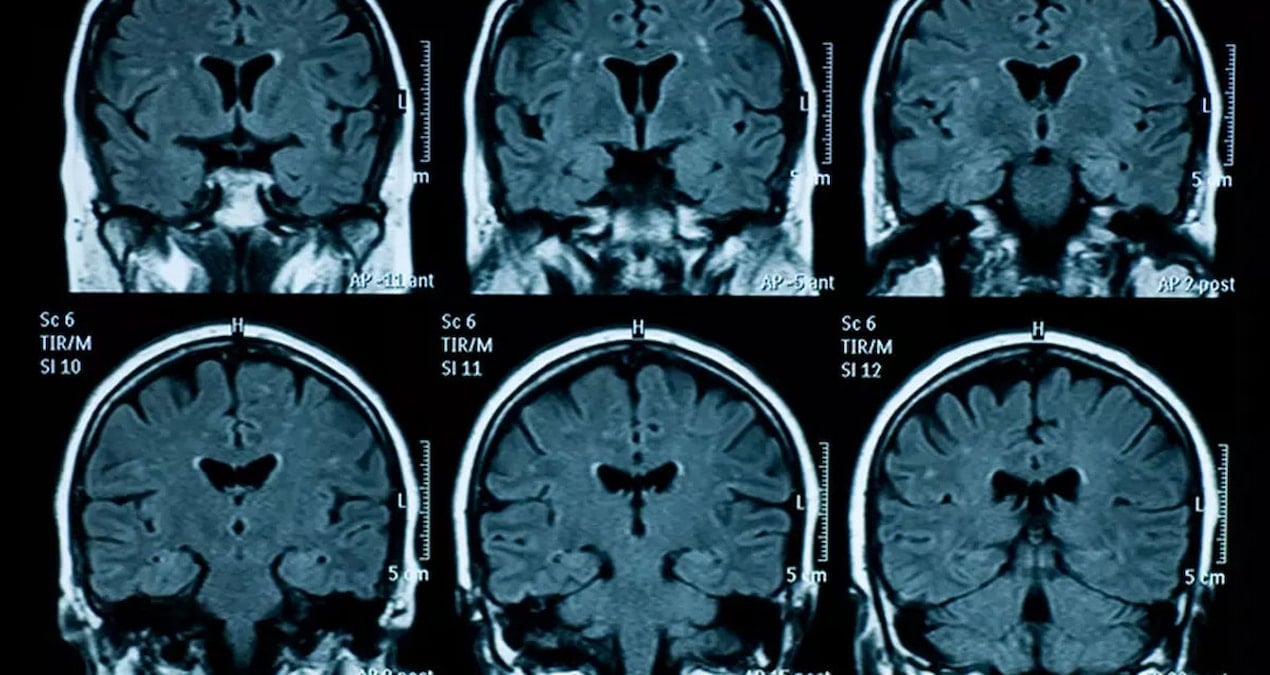

Kanada’nın Vancouver kentinde gerçekleştirilen çarpıcı bir araştırmada, epilepsi hastası olan 87 yaşındaki bir bireyin beynine odaklanıldı. Ne yazık ki, hasta beklenmedik bir şekilde kalp krizi geçirerek hayatını kaybetti. Bu süreçte, elektroensefalogram (EEG) testi sonuçlarından yararlanılarak, hastanın ölüm anındaki beyin aktivitesi incelendi. Özellikle kalbin durmasından önceki ve sonraki 30 saniye, araştırmacıların dikkatini çekti.

Bu araştırma, insanların yaşamlarının son anlarında gözlerinin önünden film şeridi gibi geçeceği fikrini destekler nitelikte. Araştırmacılar, ‘gama osilasyonlarında’ bir artış tespit etti. Gama osilasyonları, anıların geri çağrılması ve rüya görme ile ilişkili dalgalar olarak tanımlanıyor. Bu durum, hastanın ölüm anında geçmiş deneyimlerini yeniden yaşadığını düşündürüyor.

Bu araştırma, benzer beyin dalgası değişimlerinin ölüm anında farelerde de gözlemlendiğini gösteriyor; ancak bu durum insanların beyinlerinde ilk kez tespit edilmiştir. Ekip, daha keskin ve kesin sonuçlara ulaşmak için daha fazla araştırma yapılması gerektiğini belirtiyor. Çalışmanın yalnızca tek bir vaka üzerinden yürütüldüğünü ve hastanın beyninde epilepsiden kaynaklanan hasar bulunduğunu vurgulamakta fayda var. Dolayısıyla, ölüm anındaki bu beyin aktivitesinin başka bir bireyde de aynı şekilde gerçekleşip gerçekleşmeyeceği şimdilik belirsiz.